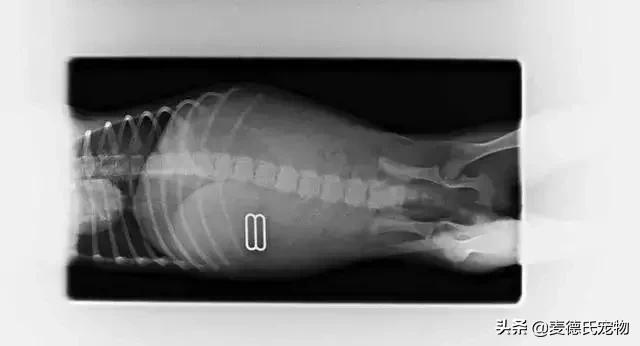

不少宠物医院也经常会放一些X光片来提醒铲屎官注意狗狗吞食异物的现象:

一只拿自己当存钱罐的汪,它专吃硬币,取出后发现它已经存了1.29美元...